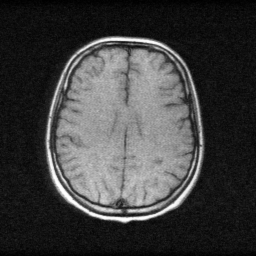

Reconstruction Gallery — 4 Scenes × 3 Scenarios

Method: CPU_baseline | Mismatch: nominal (nominal=True, perturbed=False)

Ground Truth

Measurement

Reconstruction